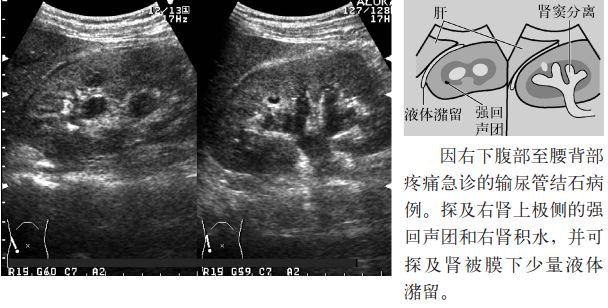

图5 肾钙化

图13 肾盂尿外渗

2.输尿管结石的间接征象是肾周围积液,是由于输尿管结石所致的肾盂内压力上升,尿液向肾盂外自然渗出所致,称为尿自然外渗。除输尿管结石外还可见于输尿管癌或输尿管转移癌、分娩及体外冲击波碎石术(extracorporeal shock wave lithotripsy,ESWL)后等。